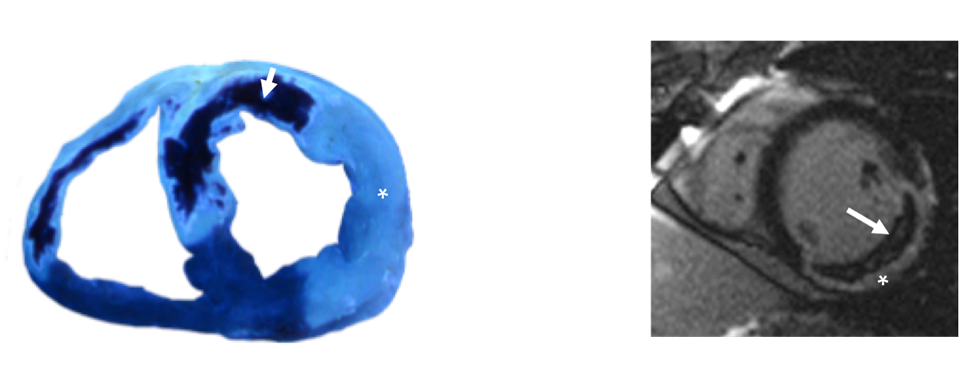

Figura

– Izquierda: Sección de un modelo experimental porcino con infarto anterior reperfundido provocado por la oclusión transitoria de la arteria descendente anterior. Se inyecta por vía intracoronaria el colorante tioflavina S. La zona bien reperfundida capta el colorante (asterisco). La zona con daño microvascular a pesar de la reperfusión coronaria no capta tioflavina (flecha).

– Derecha. Corte transversal de un estudio de resonancia magnética cardiaca en un paciente con infarto inferior provocado por la oclusión trombótica de la arteria coronaria derecha que fue reperfundido mediante angioplastia primaria y stent intracoronario. Se inyecta de manera intravenosa el colorante gadolinio. La zona infartada capta gadolinio (asterisco). El centro de la zona infartada presenta un severo daño microvascular que impide la entrada del colorante (flecha).

La resonancia magnética cardiaca (RMC) ha sido fundamental para un mejor entendimeinto y una adecuada detección del daño microvascular tras el infarto (Figura). Este hallazgo detectado mediante RMC se conoce como obstrucción microvascular (OMV). Hasta un 50% del total de los pacientes con infarto reperfundidos y hasta un 30% de aquellos con reperfusión angiográfica de la arteria epicárdica aparentemente normal presentan OMV lo cual ejerce efectos estructurales y pronósticos deletéreos2. Estudios recientes han demostrado de manera contundente que la presencia de OMV extensa en pacientes con infarto tratados con estrategias de revascularización coronaria es uno de los predictores más potentes de remodelado adverso, insuficiencia cardiaca y muerte2,3,5.

En la actualidad, el análisis mediante RMC de las secuencias de realce tardío de gadolinio representa el método de referencia para diagnosticar y cuantificar la OMV2,3,5. Unos minutos después de la inyección de contraste, el gadolinio desaparece del miocardio. La persistencia de la captación tardía de contraste permite una delimitación precisa del área infartada, mientras que la falta de contraste en la región central del territorio infartado identifica la presencia de OMV (Figura)2,3,5. Otros métodos derivados de la RMC tales como el retraso de la llegada a la zona infartada durante el primer paso tras la inyección del contraste (muy sensible pero poco específica de daño microvascular grave) o la cuantificación del flujo miocárdico (pendiente de validación) son alternativas a la valoración de la OMV mediante secuencias de captación tardía3.